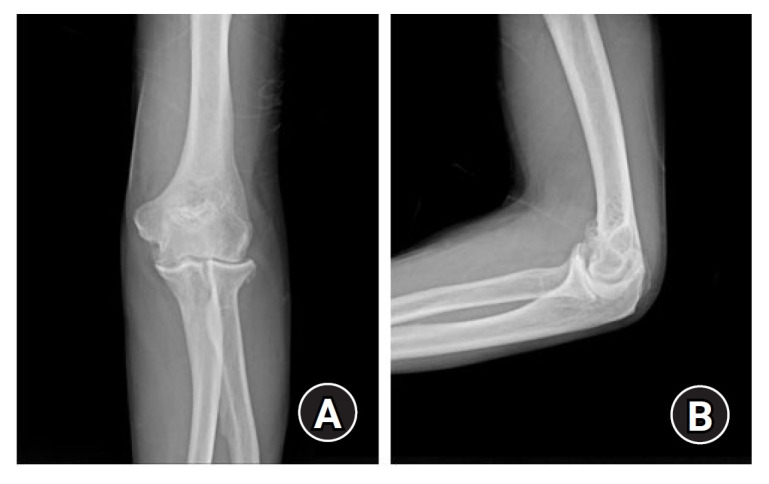

眶管综合征是指肘部周围尺神经通路受压引起的压迫性神经病。一名 63 岁的男性患者前来就诊,主诉其左手无名指和小指感觉减退和无力,并称症状最早出现在 6 个月前。大约 5 年前,他在蒙古接受了切除左肘关节神经节囊肿的手术。磁共振成像显示,之前的手术部位有一个囊性肿块,压迫了肘管内的尺神经。患者接受了尺神经减压术和前方转位术,并切除了囊性肿块。经病理检查,肿块被诊断为神经节囊肿。随访一年后,患者的感觉功能障碍和乏力等症状有所改善。本报告描述了一例罕见的神经节囊肿复发病例,该病例曾接受过神经节囊肿切除术,但复发后压迫了肘隧道内的尺神经。

Cubital tunnel syndrome refers to compression neuropathy caused by pressure on the ulnar nerve pathway around the elbow. A 63-year-old male patient visited the clinic complaining of decreased sensation and weakness in his left ring finger and little finger, stating that the symptoms first began 6 months prior. He had undergone surgery to remove a ganglion cyst from his left elbow joint about 5 years prior in Mongolia. Magnetic resonance imaging revealed a cystic mass located at the previous surgical site, which was compressing the ulnar nerve within the cubital tunnel. Ulnar nerve decompression and anterior transposition were performed, and the cystic mass was excised. Upon pathological examination, the mass was diagnosed as a ganglion cyst. The patient's symptoms including sensory dysfunction and weakness improved over the 1-year follow-up period. This report describes a rare case of ganglion cyst recurrence compressing the ulnar nerve in the cubital tunnel after previous ganglion cyst excision.